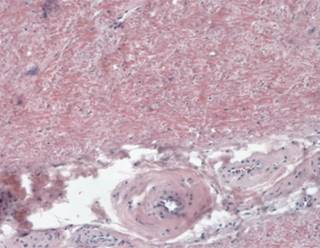

Figure 7: On the surface there are areas of frayed appearance, which correspond to the areas of fibrillar degeneration.